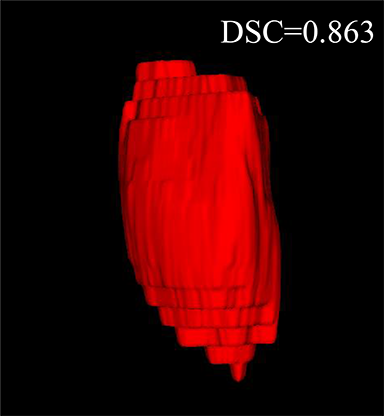

Comparison with ground truth. Some predicted results of MMFNet are shown in 2D images and 3D images in Figure 7 and Figure 8. As shown in these figures, although the shape and size of NPC are varied from each other, MMFNet can still accurately determine the regions of NPC and obtain the accurate contours of tumors. Through analyzing 2D images in figure 7, MMFNet has a capacity to fuse multi-modality MRI to reduce the confusion brought by intensity’ similarity between nearby tissues and NPC. The values of , and of MMFNet are shown in Table 1. MMFNet can reach the best results with , and .

Comparison with related works. Table 1 reports the values of , and for different methods. Predicted masks of different methods are illustrated in Figure 9 and Figure 10, which respectively present results in 2D and 3D images. Through comprehensively analyzing these results, the proposed MMFNet actually have the following properties:

(i) It directly fuses 3D MRI images rather than 2D slices. Thus, it can effectively use meaningful information from neighboring slices of MRI to realize NPC segmentation. As shown in Table 2, MMFNet can bring , and improvements in and compared to the best method based on 2D images (Multi-modality patch-based CNN). And Figure 10 shows that 3D-based methods have less isolated regions (false positives) than 2D-based ones.

(ii) It segments NPC by fusing multi-modality MRIs with the multi-encoder network. Thus, it can learn complementary and interdependent features from different modalities of MRI for final decisions. Additionally, comparing with input-level fusion networks and decision-level fusion networks, layer-level fusion networks (including MMFNet) can effectively capture informative features from different modalities of MRI and fuse low-level features and high-level features.

(iii) It uses a fusion block to fuse low-level features from different modalities of MRI and prepare these low-level features for the fusion with high-level features. Thus, it can more effectively fuse information from various sources. It also uses the self-transfer strategy to initialize the netwerk. Hereby, it can stimulate encoders to make full mining of meaningful features from modality-specific MRI. And it finally improve base multi-encoder-based network (Merging encoders’ fetures) by , and in and .